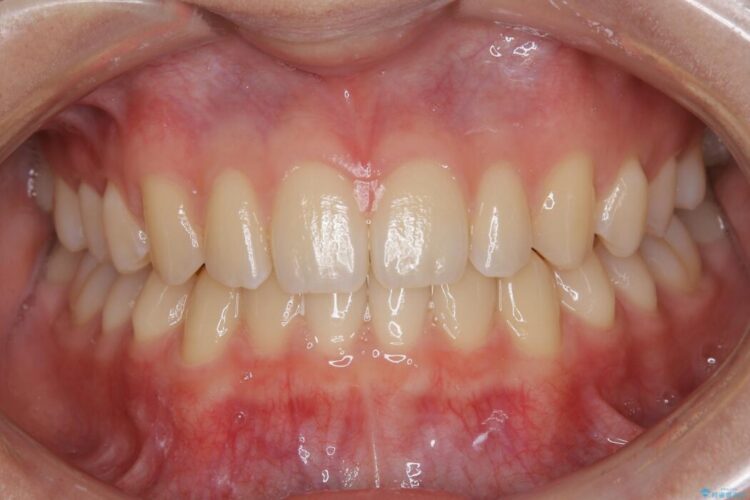

すきっ歯を改善したいとご来院された患者様です。

マウスピース14枚・期間4ヶ月で主訴であるすきっ歯を改善し、治療を終えることが出来ました。